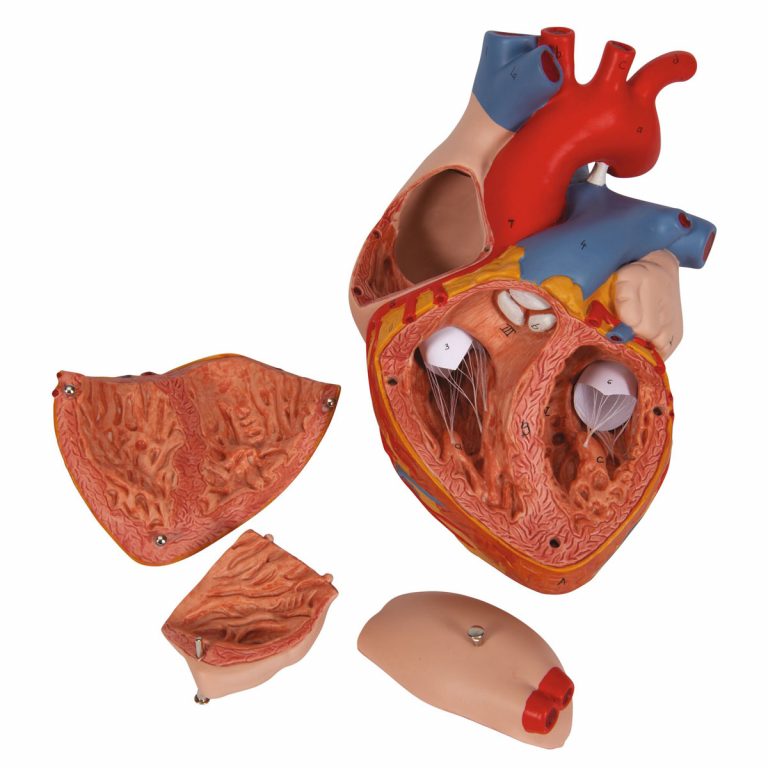

Фотографии и 3D-модели анатомии сердца человека